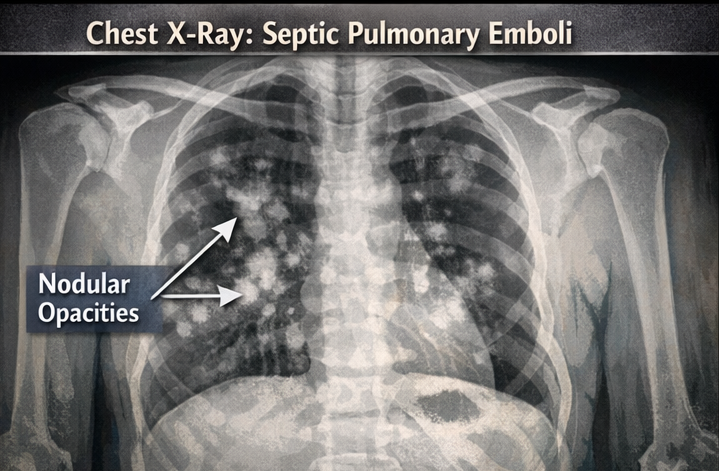

Radiological Evaluation:

• Chest X-ray showed multiple bilateral nodular opacities suggestive of septic pulmonary emboli. These findings fulfilled the modified Duke criteria for definite infective endocarditis.